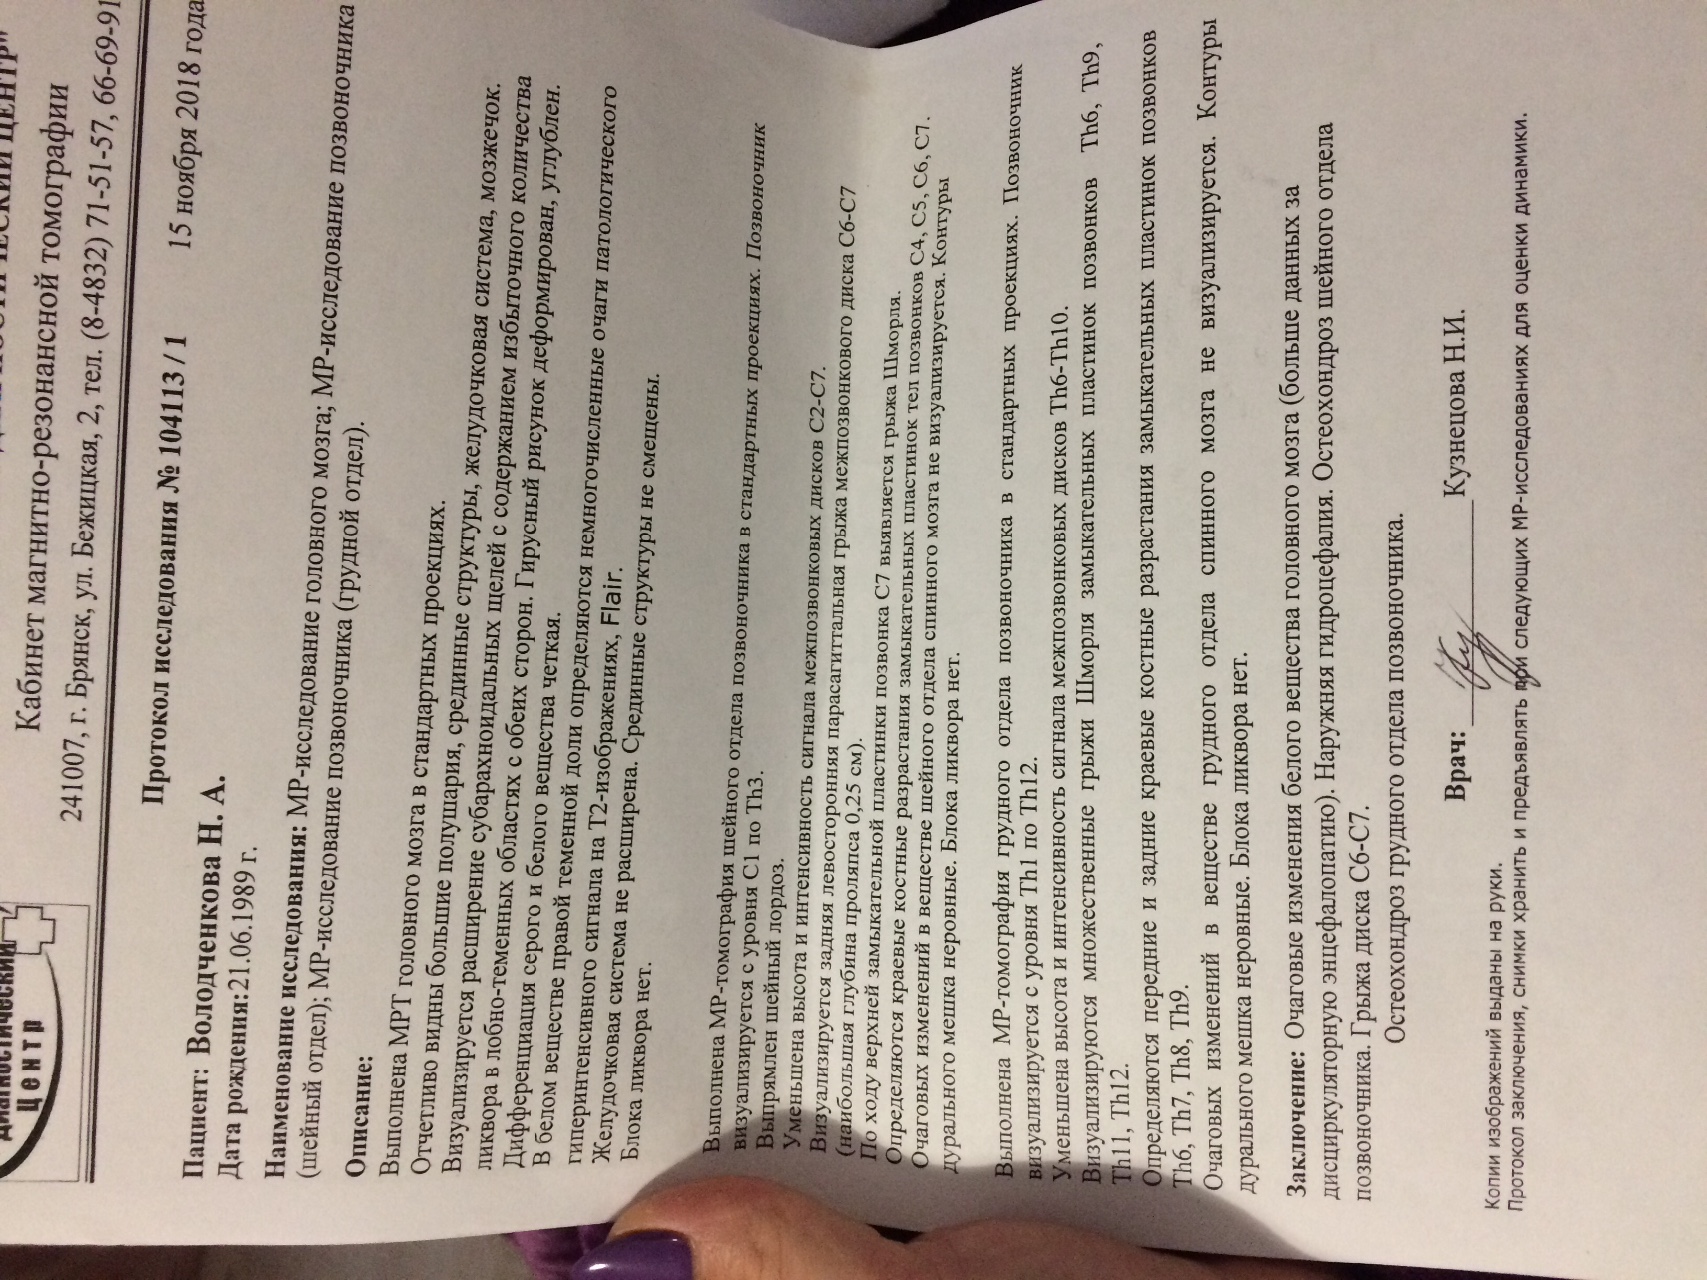

МРТ головного мозга: Расшифровка снимков и Интерпретация

Раздел: Визуальные уроки